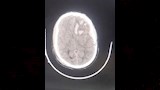

أعلنت مديرية الشئون الصحية بمحافظة الدقهلية، اليوم السبت، نجاح فريق طبي بمستشفى السنبلاوين العام في إنقاذ حياة مريض يبلغ من العمر 42 عامًا، بعد إصابته بنزيف حاد بالمخ وكسور بعظام الجمجمة نتيجة حادث طريق.

وقال بيان لمديرية الصحة بالدقهلية أن المريض قد وصل إلى استقبال المستشفى وهو يعاني من اضطراب شديد في درجة الوعي ونزيف من الأنف والأذن، وتم على الفور تقديم الإسعافات الأولية اللازمة وإجراء الفحوصات الطبية، التي أظهرت وجود كسور متعددة بالجمجمة ونزيف داخلي بالمخ وجرى حجز المريض بوحدة العناية المركزة، وبعد 6 ساعات من المتابعة الدقيقة، تبين زيادة حجم النزيف وتدهور مستوى الوعي، مما استدعى التدخل الجراحي العاجل.

وخلال العملية جرى رفع عظام الجمجمة لإزالة الانضغاط عن أنسجة المخ، وتكللت الجراحة بالنجاح، والمريض الآن تحت العلاج والمتابعة بالقسم الداخلي.